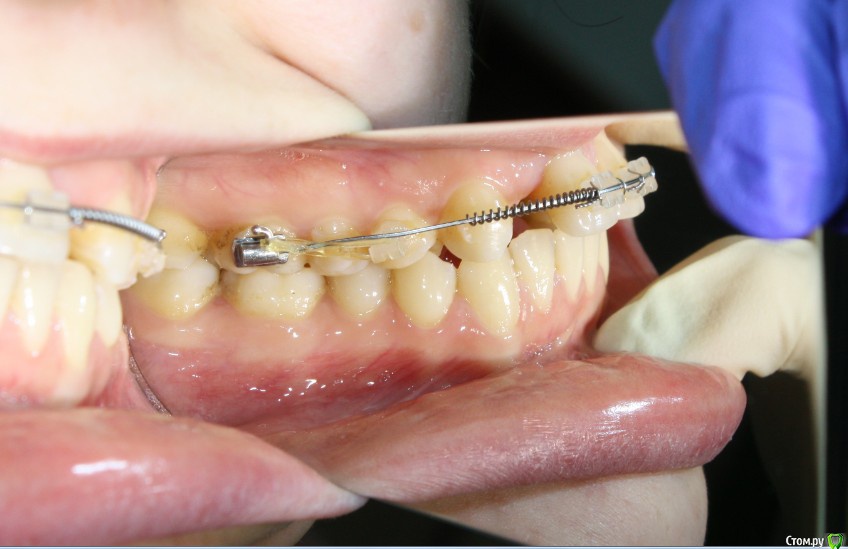

Здравствуйте коллеги! На консультацию обратилась пациентка, сейчас находится на ортодонтическом лечении. Предистория: три года назад обратилась к стоматологам с жалобой на неудовлетворительную эстетику фронтального отдела, вследствие врожденного отсутствия латеральных резцов. Ей было предложено ортодонтически создать место для боковых резцов, затем провести имплантацию и протезирование на имплантатах 12, 22.

Затем, с ее слов, идет длительный этап ортодонтии, почти 3 года, вследствие которого получили немного места для двоек, которого не достаточно для иплантации, так же центральные резцы ушли вперед, образовалась саггитальная щель.

Фото сегодня:post-461-0-94195200-1456407270_thumb.jpgpost-461-0-97652100-1456407271_thumb.jpgpost-461-0-40898500-1456407273_thumb.jpgpost-461-0-68973300-1456407274_thumb.jpgpost-461-0-88108800-1456407275_thumb.jpgpost-461-0-99061300-1456407276_thumb.jpgpost-461-0-92547500-1456407277_thumb.jpgpost-461-0-02811200-1456407279_thumb.jpgpost-461-0-05035300-1456407280_thumb.jpgpost-461-0-27197600-1456407281_thumb.jpg